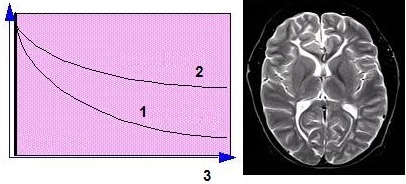

Each echo is used to create a different image, usually displaying different image contrast. The images below were acquired using a Spin Echo variable echo sequence. The first echo displays PD-weighting, while the second echo displays T2-weighting.

| Number | Description |

|---|---|

| 1 | First echo |

| 2 | Second echo |

T1 is the time constant for longitudinal relaxation and thermal or spin lattice relaxation. Scan protocols that allow the T1 effects to predominate over the other relaxation effects produce T1-weighted images. In T1-weighted images, tissues with short T1 are bright and tissues with long T1 are dark. In the brain, white matter is brighter than gray matter, and CSF is dark.

| 1 | Short T1 (fat) |

| 2 | Long T1 (water) |

| 3 | Time or TR period |